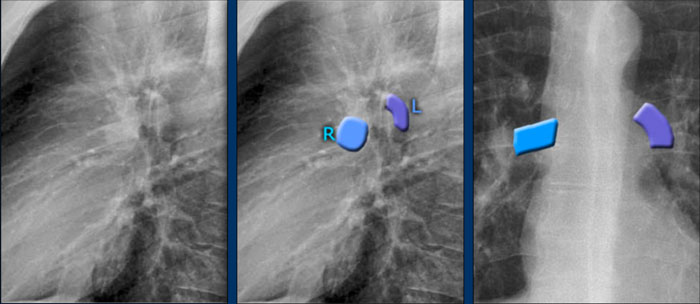

Pulmonary Vasculature and Hilar Structures

The left pulmonary artery (shown in purple) arches above the left main bronchus and is situated higher than the right pulmonary artery (in blue), which courses anterior to the right main bronchus.

Understanding normal hilar anatomy on the lateral view facilitates detection of abnormalities.

For example:

• On the PA view, hilar enlargement may be noted, but it can be difficult to differentiate between vascular dilatation and lymphadenopathy.

• On the lateral view, the presence of rounded opacities in regions where pulmonary vessels are not normally seen strongly suggests enlarged lymph nodes.

In this case, the patient was diagnosed with sarcoidosis.

Additionally, note the widened paratracheal stripe, another indicator of mediastinal lymphadenopathy.